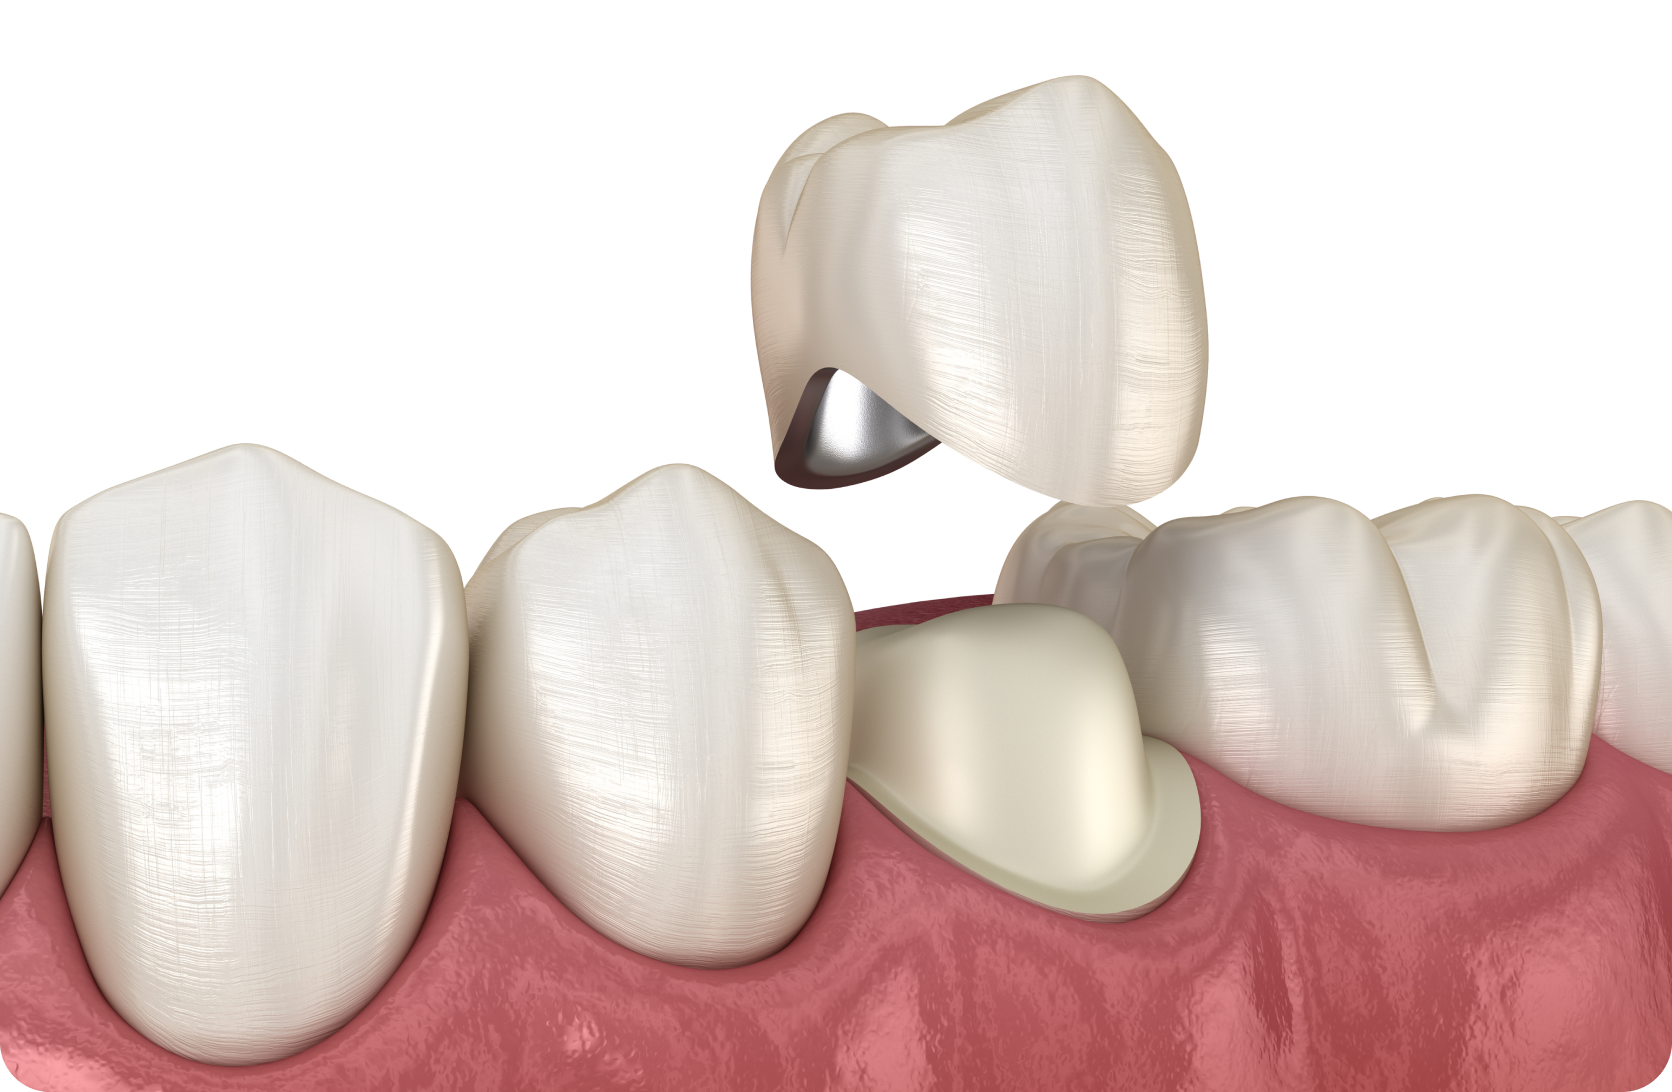

저희 범석영치과는 일반적인 치과 치료에

자신 있게 내세울 수 있는 ‘특화 진료’를 더해,

환자 중심의 진료 서비스를 제공합니다.